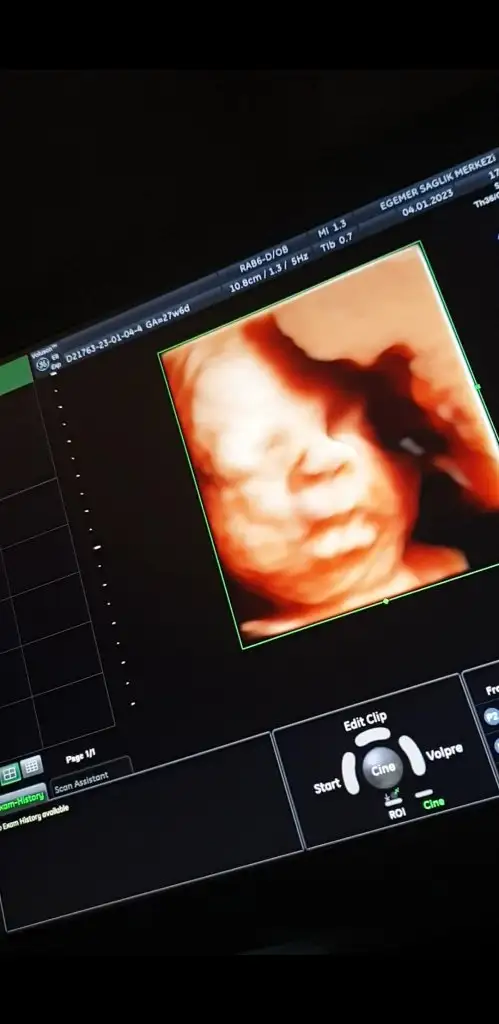

Kızlar iyi akşamlar, biraz önce kontrolden geldim, sat a göre 27+6 ama ultrasonda 27+4 çıktı, bebeğim 1120 gr - 36 cm olmuş🥰 rahim ağzı uzunluğum 4 cm üzeri çıktı.

Herşey yolunda gidiyor çok şükür, inşallah hiçbir problem çıkmadan hepimiz sağlıcakla doğururuz🙏

Video çekmiştim ondan kareler aldım😍

Her dururuşu bebeği değiştiriyor.

Screenshot_20230104-182322_Photos.jpg Screenshot_20230104-182558_Photos.jpg Screenshot_20230104-181937_Photos.jpg

Eki Görüntüle 3186715 Eki Görüntüle 3186714 Eki Görüntüle 3186716